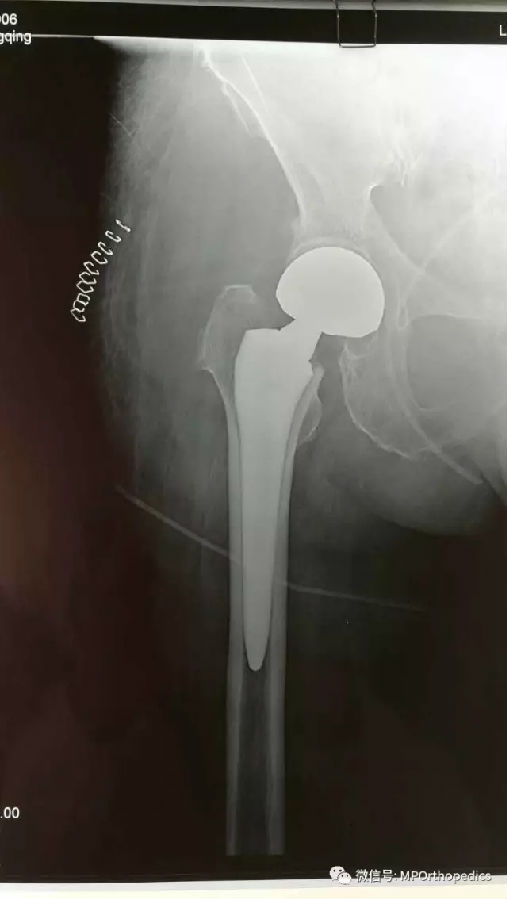

本次受益于此手术的患者是78岁右侧股骨颈骨折的男性病人,侯德才主任术前综合评估患者情况后,详细规划好术前计划,术中采用的SuperPath TM入路(5.5cm切口),经由梨状肌,臀小肌间隙入路,借助经皮穿刺套管完成髋臼的骨准备及人工关节组建的安装,术中不切断任何肌肉组织和肌腱,完整的保留了短外旋肌群,且缝合复原关节囊,大大降低了病人术后髋关节后脱位的风险。病人麻醉苏醒后能早期下床进行全范围的功能锻炼。

术后X光片